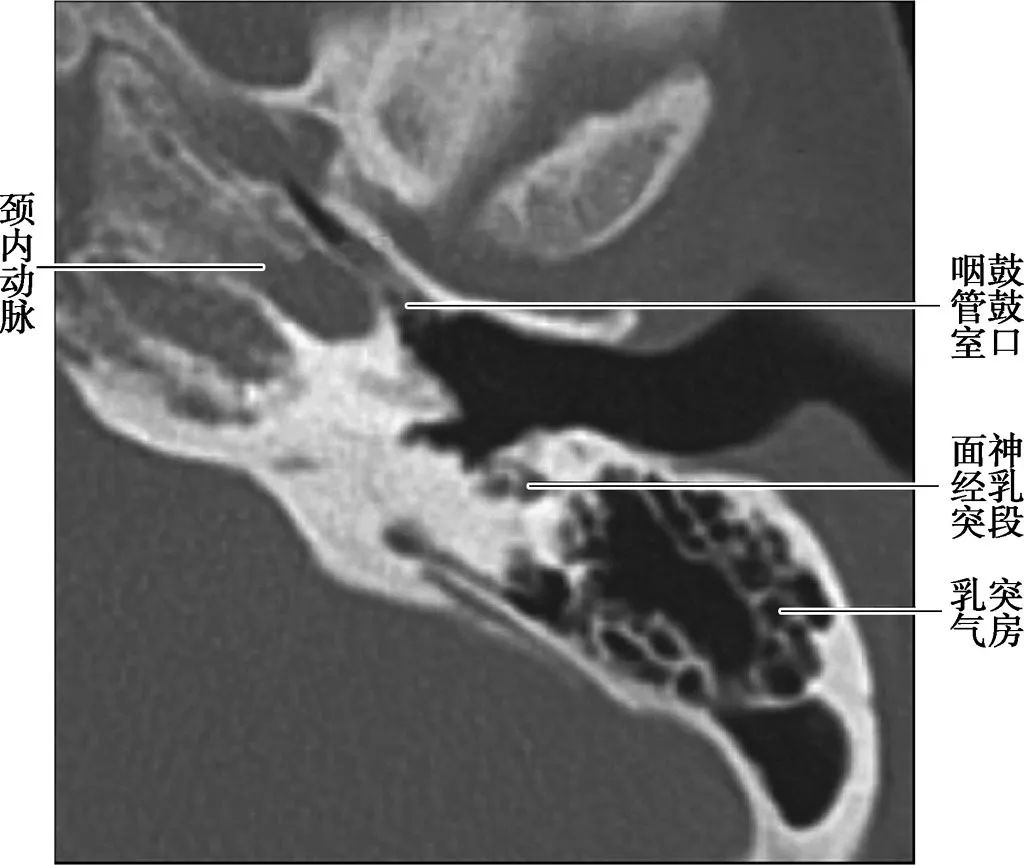

(CT横断面自下至上两个层面)

咽鼓管结构

A. CT;B. MRI

咽鼓管为连接鼻咽腔与鼓室的通道,向内通鼻咽腔,开口于咽鼓管咽口,向外通鼓室前壁,开口于咽鼓管鼓口,鼻咽癌可经咽鼓管侵入中耳。